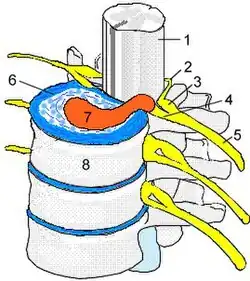

Der Bandscheibenvorfall (lateinisch Prolapsus nuclei pulposi, ärztlich oft Nucleus-pulposus-Prolaps, kurz NPP), auch Bandscheibenprolaps (BSP), Bandscheibenhernie, Discushernie (oder Diskushernie) und Discusprolaps, ist eine Erkrankung der Wirbelsäule, bei der Teile der Bandscheibe in den Wirbelkanal – den Raum, in dem das Rückenmark liegt – vortreten. Im Gegensatz zur Bandscheibenprotrusion (Vorwölbung) wird beim Prolaps der Faserknorpelring der Bandscheibe (Anulus fibrosus) ganz oder teilweise durchgerissen, während das hintere Längsband (Ligamentum longitudinale posterius) intakt bleiben kann (sogenannter subligamentärer Bandscheibenvorfall).

Bandscheiben sind bradytrophe Gewebe, das heißt, sie werden nicht direkt aus dem Blutkreislauf heraus mit Nährstoffen versorgt, sondern durch Diffusion. Hierbei spielen semipermeable Membranen, welche die Knorpelringe voneinander trennen, die entscheidende Rolle. Durch Scherkräfte können diese Membranen einreißen, wodurch sie ihre Funktion verlieren und die Bandscheibe nebst Gallertkern der Bandscheibe (Nucleus pulposus) austrocknet (black disc lesion). Wenn es zu einem Bandscheibenvorfall kommt, ist der Gallertkern praktisch nicht mehr in seiner ursprünglichen Form vorhanden. Der Bandscheibenvorfall entsteht also zumeist auf dem Boden einer langjährigen Vorschädigung der Bandscheibe. Der Gallertkern (ca. 80 % Wasser) besteht bei der gesunden Bandscheibe aus einem gallertigen, zellarmen Gewebe und übernimmt bei Belastung zusammen mit den Knorpelringen und den Membranen die Funktion einer hydraulischen Kugel („Wasserkissen“). Die Wirbelkörper und Bandscheiben vorne ermöglichen zusammen mit den kleinen Wirbelgelenken hinten („Facettengelenke“) die hohe Beweglichkeit der gesamten Wirbelsäule und ihre hohe Stabilität.

Typischerweise verursachen Bandscheibenvorfälle Rückenschmerzen (Lumbalgie) mit oder ohne Ausstrahlung in die Beine (Ischialgie) oder in die Arme (Brachialgie). Bei der mediolateralen Diskushernie werden tiefliegende Nerven komprimiert. Je nach Schwere der Symptomatik kann es dann auch zu einem Taubheitsgefühl oder zu einem Muskelausfall im Versorgungsgebiet der eingeklemmten Nervenwurzel kommen.[8]